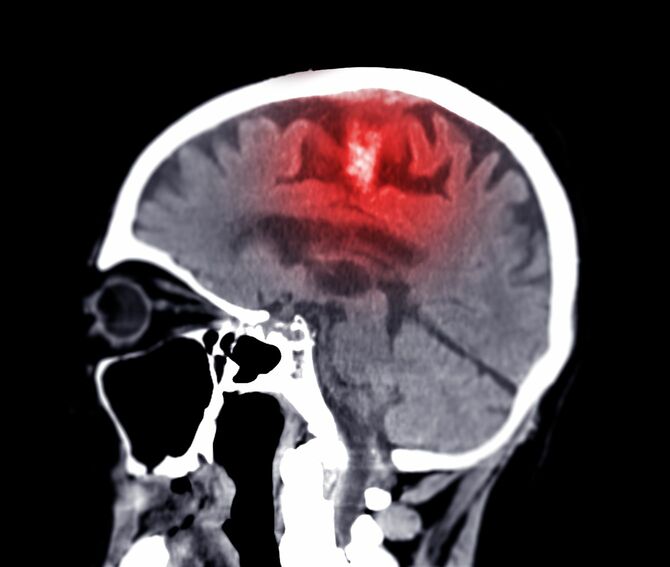

認知症の原因はたくさんあります。なかには治療すれば治るものもありますが、大半を占めるのは、加齢とともに進行するアルツハイマー病です。

脳はさまざまな要因でダメージを受けていて、それらから脳を守ろうとしてアミロイドβが発生しています。製薬会社はアミロイドβを除去する(たまらない)薬を開発しようとしていますが、問題はアミロイドβではありません。アミロイドβがたまる要因となる、脳の神経細胞にダメージを与える根本的な要因を防ぐ必要があるのです。

脳で炎症が起こったり、栄養不足に陥ったり、毒物が蓄積したりすることで、神経細胞がダメージを受け、認知機能がどんどん低下していくのですから、それらをできるだけ避けることができれば、認知機能の低下防止につながると考えられます。「炎症」「栄養不足」「毒物」への対策は特別なものではありません。ふだんの生活習慣、特に食事に気をつけること、生活環境を整えることで予防できるものが多くあります。